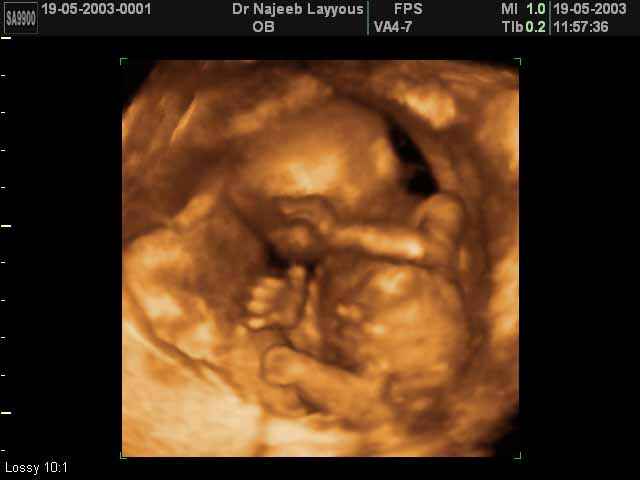

- Fetal Behavior Ultrasound Photos

Ultrasound Photos in 3D showing Fetal Behavior Inside the uterus | Dr N Layyous